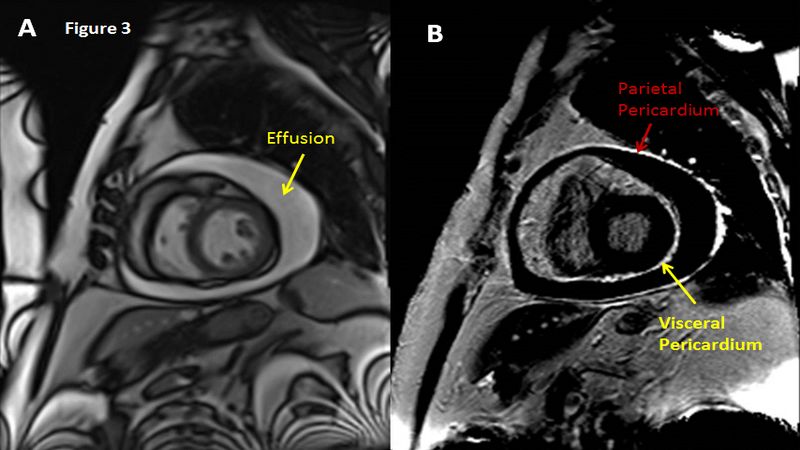

- Chụp MRI tim: Đánh giá chuyên sâu tình trạng tràn dịch màng ngoài tim và sự chèn ép tim do màng ngoài tim dày lên.

Chụp MRI tim giúp đánh giá tình trạng tràn dịch màng ngoài tim hiệu quả